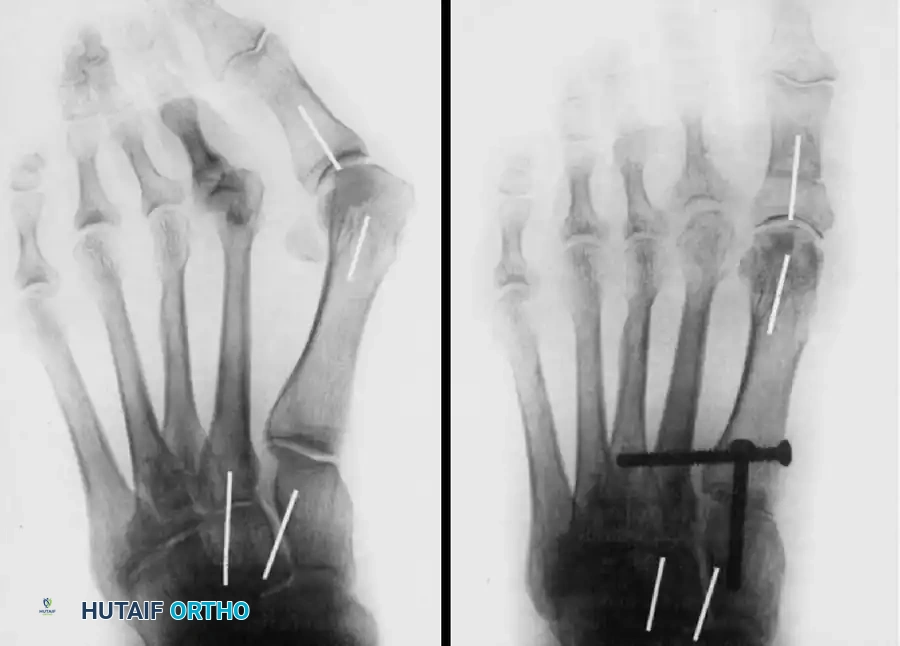

Step 5: Provisional Fixation and Alignment Verification

Manually reduce the deformity. The first metatarsal should plantarflex and adduct. Hold the metatarsal in the corrected position with a 0.062-inch Kirschner wire driven from the dorsal-distal first metatarsal into the plantar-proximal medial cuneiform.

Verify the correct positioning of the metatarsal with intraoperative fluoroscopy. Check the AP view for closure of the IMA and the lateral view to ensure the first metatarsal is plantarflexed relative to the talonavicular axis.

Image

FIGURE 81-63F: Final correction obtained, demonstrating restoration of the intermetatarsal angle and a congruent first MTP joint.